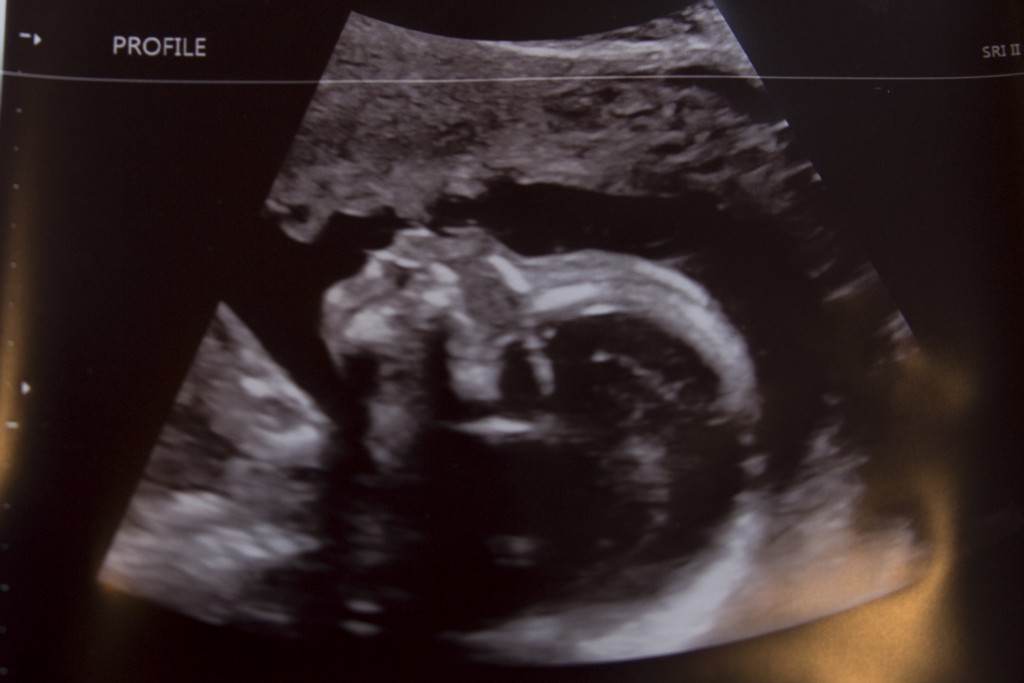

And a cute picture of his profile